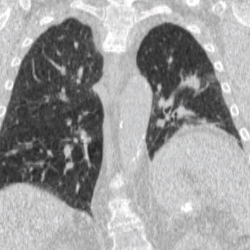

4DCT is used in radiation therapy planning to reduce doses to healthy organs such as the heart or lungs. Most radiation therapy is planned using the results of a 3D CT scan. A 3D scan largely presents a snapshot of the body at a particular point in time, however due to the time of the acquisition, in which the patient is likely to have moved in some way (even if only breathing), there will be an element of blurring or averaging in the 3D scan.[6] When it comes to treatment planning, this motion can mean there is less accuracy in the positioning of treatment beams, and reduce the likelihood of a repeatable set-up on the linear accelerator when it comes to treatment.[7]

To minimise physical movements of the patient, some sort of immobilisation is typically used. To overcome physiological motion, such as breathing, 4DCT acquires images at a range of times and positions, allowing the extent of motion to be visualised (e.g. from maximum inspiration to maximum exhalation). The treatment plan can then be designed with a knowledge of the full range of possible positions of important organs, and the tumour (target) itself.[8]

4DCT will usually involve a gating technique, such as breathing tracking, so that image acquisition is automatically triggered at set points.[9] This gating can also be applied at treatment, where the radiotherapy beam is only switched on at certain points in the breathing cycle (as in the deep inspiration breath-hold technique).[10]